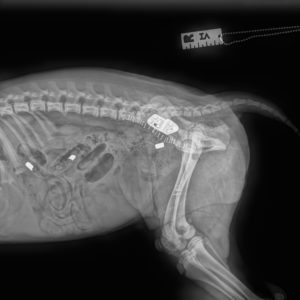

Osteotomia klinowa doczaszkowa kości piszczelowej w leczeniu zerwania więzadła krzyżowego doczaszkowego u psów

W czasopiśmie „Weterynaria w praktyce” (wydanie nr 1-2/2021) ukazał się artykuł z naszym udziałem na temat osteotomii klinowej doczaszkowej kości piszczelowej.